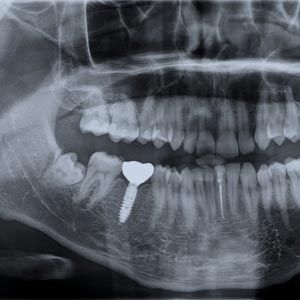

Because implants are priced separately, the number you receive will be one of the most significant factors affecting the cost of your treatment. Typically, you will need one for a crown, two or more for a bridge, and four or more for a denture. Each dental implant requires an abutment (a device that connects the implant to the restoration).

Preparatory Procedures

If you have suffered jaw recession, you may need a bone graft or sinus lift before implant placement. Additional procedures will add to the overall cost of rehabilitating your smile.